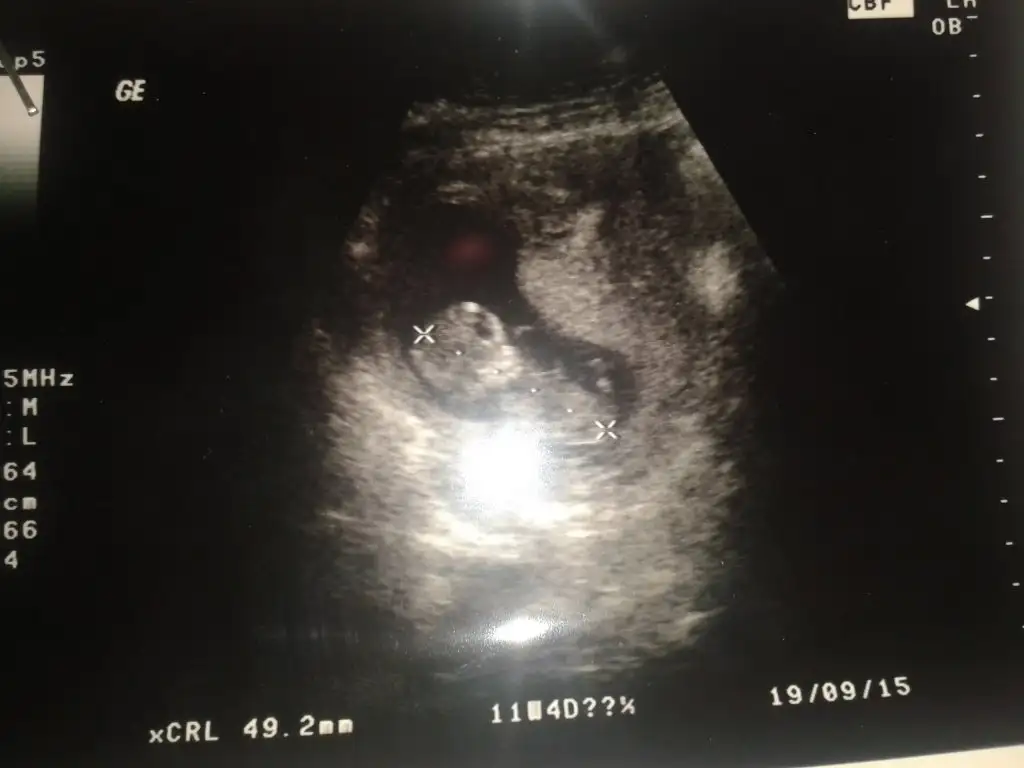

arkadaslar benimn bebisimede tahmın yapabilirmisiniz rica etsem :/

• 20150225_130514.webp

20150225_130514.webp

19,8 KB · Görüntüleme: 125